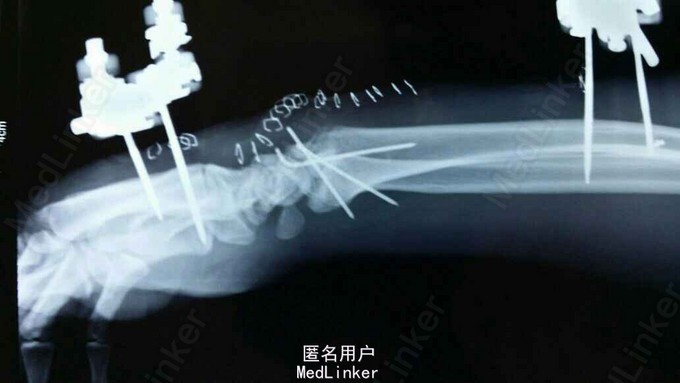

诊断:双尺桡骨远端粉碎性骨折 治疗:入院后,给予手法复位夹板固定,左手神经症状明显缓解,给予对症治疗,消肿后,于2015年8月27日行手术治疗。

请问大家,对于这种骨折是行外架+克氏针固定好,还是钢板固定好?